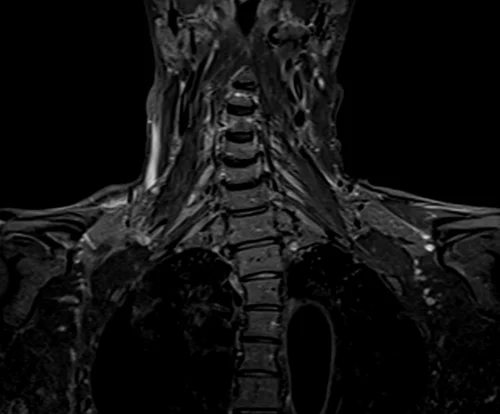

BRACHIAL PLEXUS